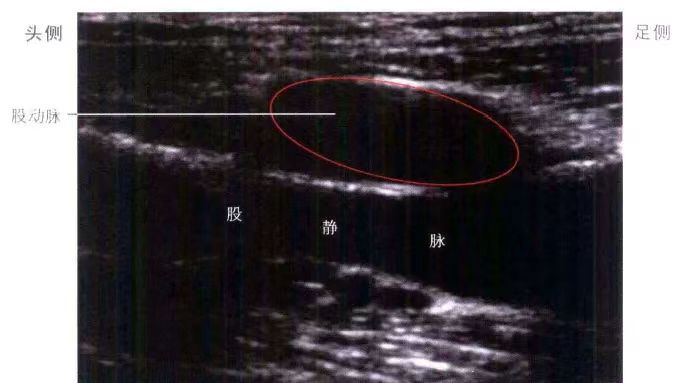

B超图像纵截面,将探头和股部平行放置,探头一端位于腹股沟韧带水平。向内或外侧平移探头,找股静脉和股动脉。

定好股静脉穿刺点进行临床教学。